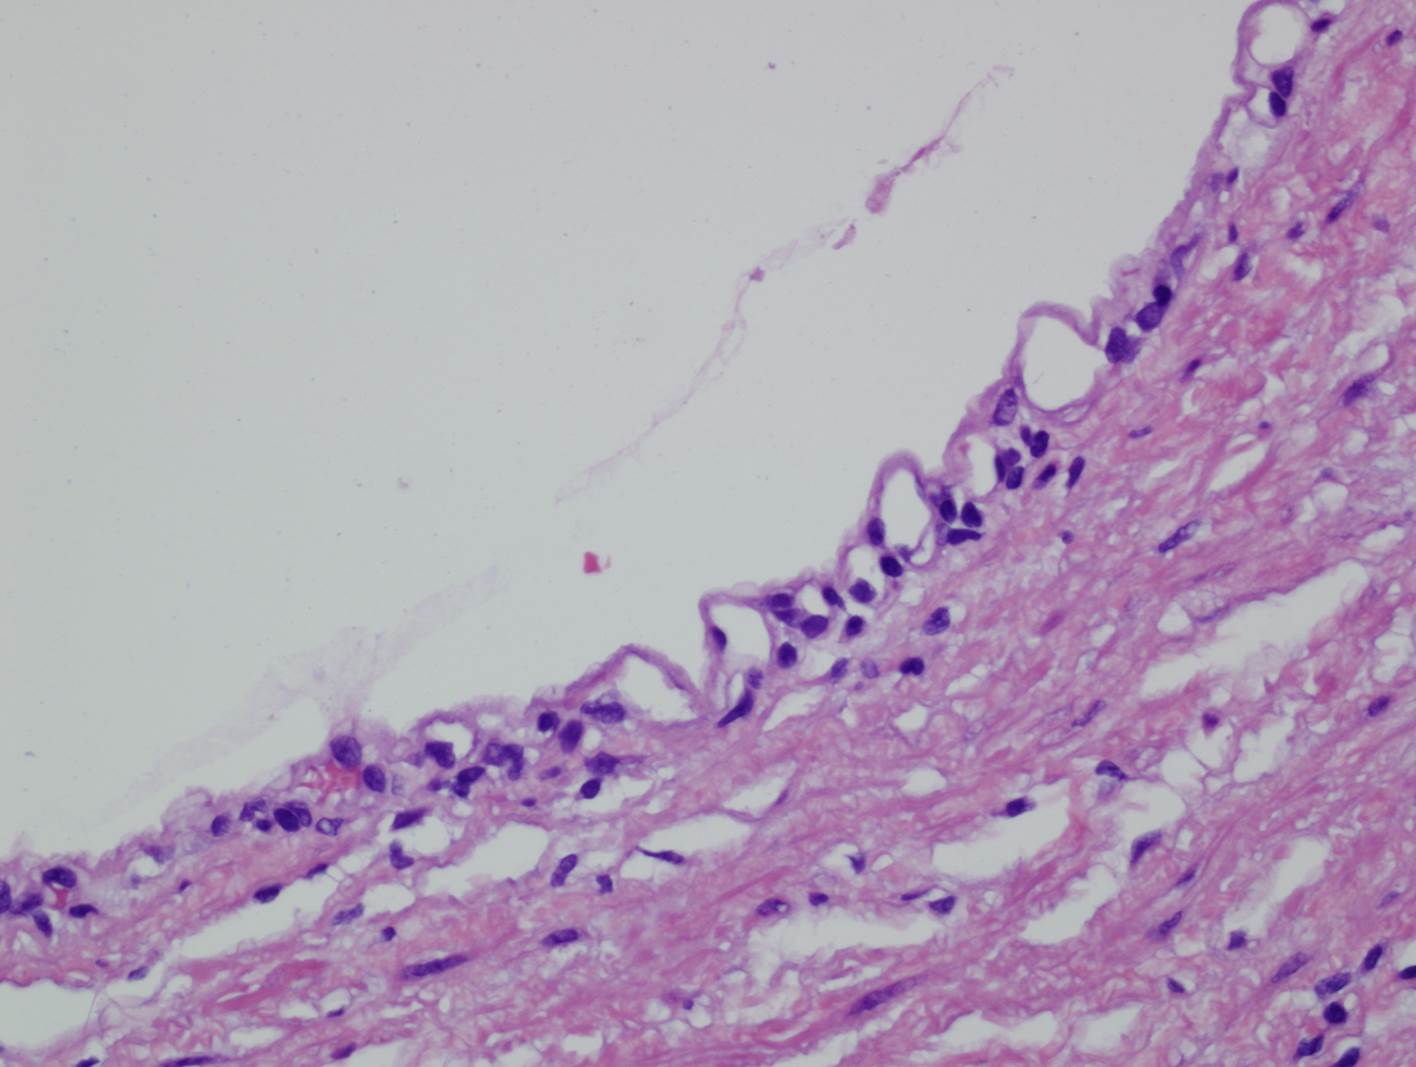

Classification of renal tumors

Case ID: 809